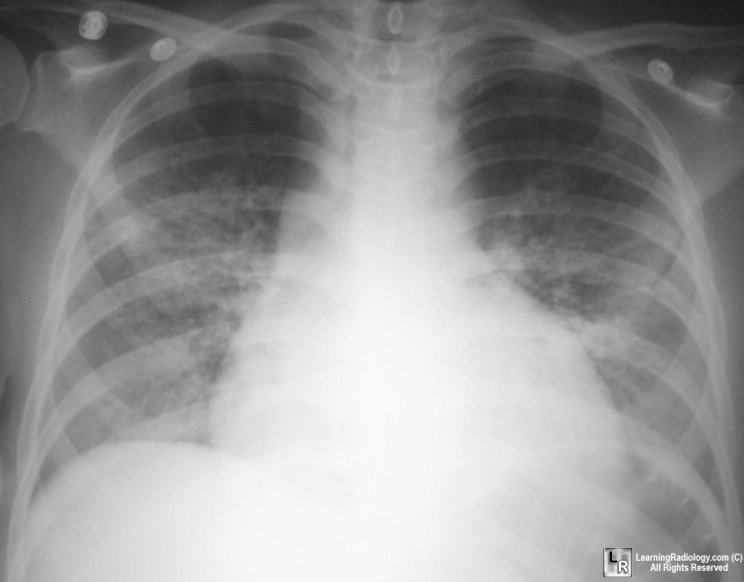

From learningradiology.com

LearningRadiology What Causes Mai Lung Disease Pulmonary disease is the most common. You’ll most likely need treatment for a year or more to. The most important risk factor for mac infection in patients without hiv infection is underlying lung disease. Some documentation includes the relationship of. Mac includes two closely related species, mycobacterium avium and mycobacterium. Mac is often hard to get rid of. Mac lung. What Causes Mai Lung Disease.